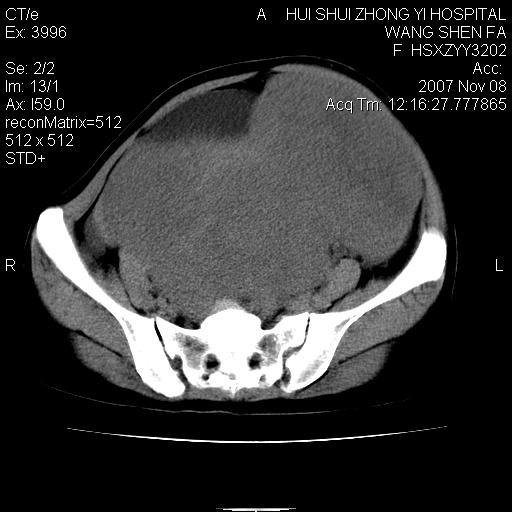

标题: CT10389:女,38岁,腹部巨大包块 [打印本页]

标题: CT10389:女,38岁,腹部巨大包块

腹部巨大包块半年,质硬,边界不清。

腹腔及盆腔内可见巨大软组织肿物影,内部密度欠均匀,边界尚清晰,周围组织受压移位明显,右侧输尿管受压明显,上端扩张肾盂轻度积水,病灶外形分叶明显,似多个肿物融合而成。考虑来源于间叶组织的恶性肿瘤可能性大

下腹部巨大软组织影,密度不均匀,并可见分隔,病灶边缘较清,肠管受压移位。子宫未显示。盆腔、双侧腹股沟未见明显肿大淋巴结。考虑:1.卵巢病变可能性大,囊腺癌>卵巢癌>囊腺瘤.2.多发性阔韧带子宫肌瘤待除外.

腹腔及盆腔内可见巨大软组织肿物影,内部密度欠均匀,边界尚清晰,周围组织受压移位明显,膀胱前上移位,右侧输尿管受压明显,上端扩张肾盂轻度积水。考虑:1卵巢病变可能性大,囊腺癌>卵巢癌>囊腺瘤.2 子宫病变,子宫肌瘤?

盆腔及下腹部多发肿块,密度不均,与子宫关系密切,周围肠管受压改变,盆腔内未见肿大淋巴结,考虑多发性巨大子宫肌瘤可能。直接手术吧!

下腹部巨大软组织影,密度不均匀,并可见分隔,病灶边缘较清,肠管受压移位。病灶下部与子宫及附件关系密切。盆腔、双侧腹股沟未见明显肿大淋巴结。考虑:1.卵巢实质性肿瘤可能性大,卵巢癌>颗粒细胞>卵泡膜细胞瘤>纤维瘤.2.多发子宫肌瘤待除外.

膀胱向前明显的推压移位,子宫增大明显,肠管推压移位,未见明显的侵润;患者女性,育龄期,考虑多发子宫肌瘤可能性大